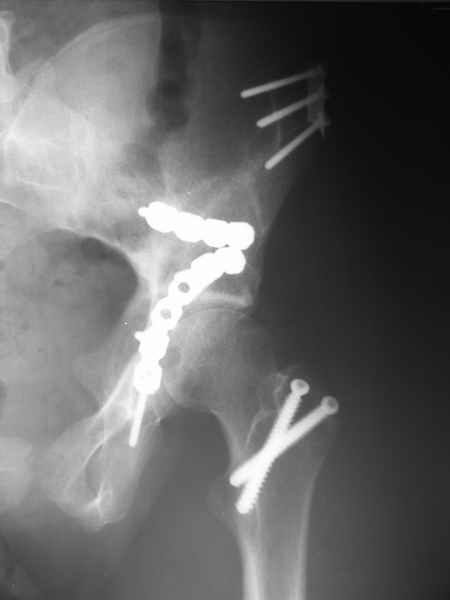

Посылаю схемы и 3D реконструкцию подобного повреждения. Называется он полным высоким двухколонным переломом вертлужной впадины, а "переломы крыла и тела подвздошной кости" входят в это понятие.

Вариантов остеосинтеза много (можно и не оперировть, т.к. конгруентность при таких переломах как правило сохраняется)

прикладываю схему доступа и случай.